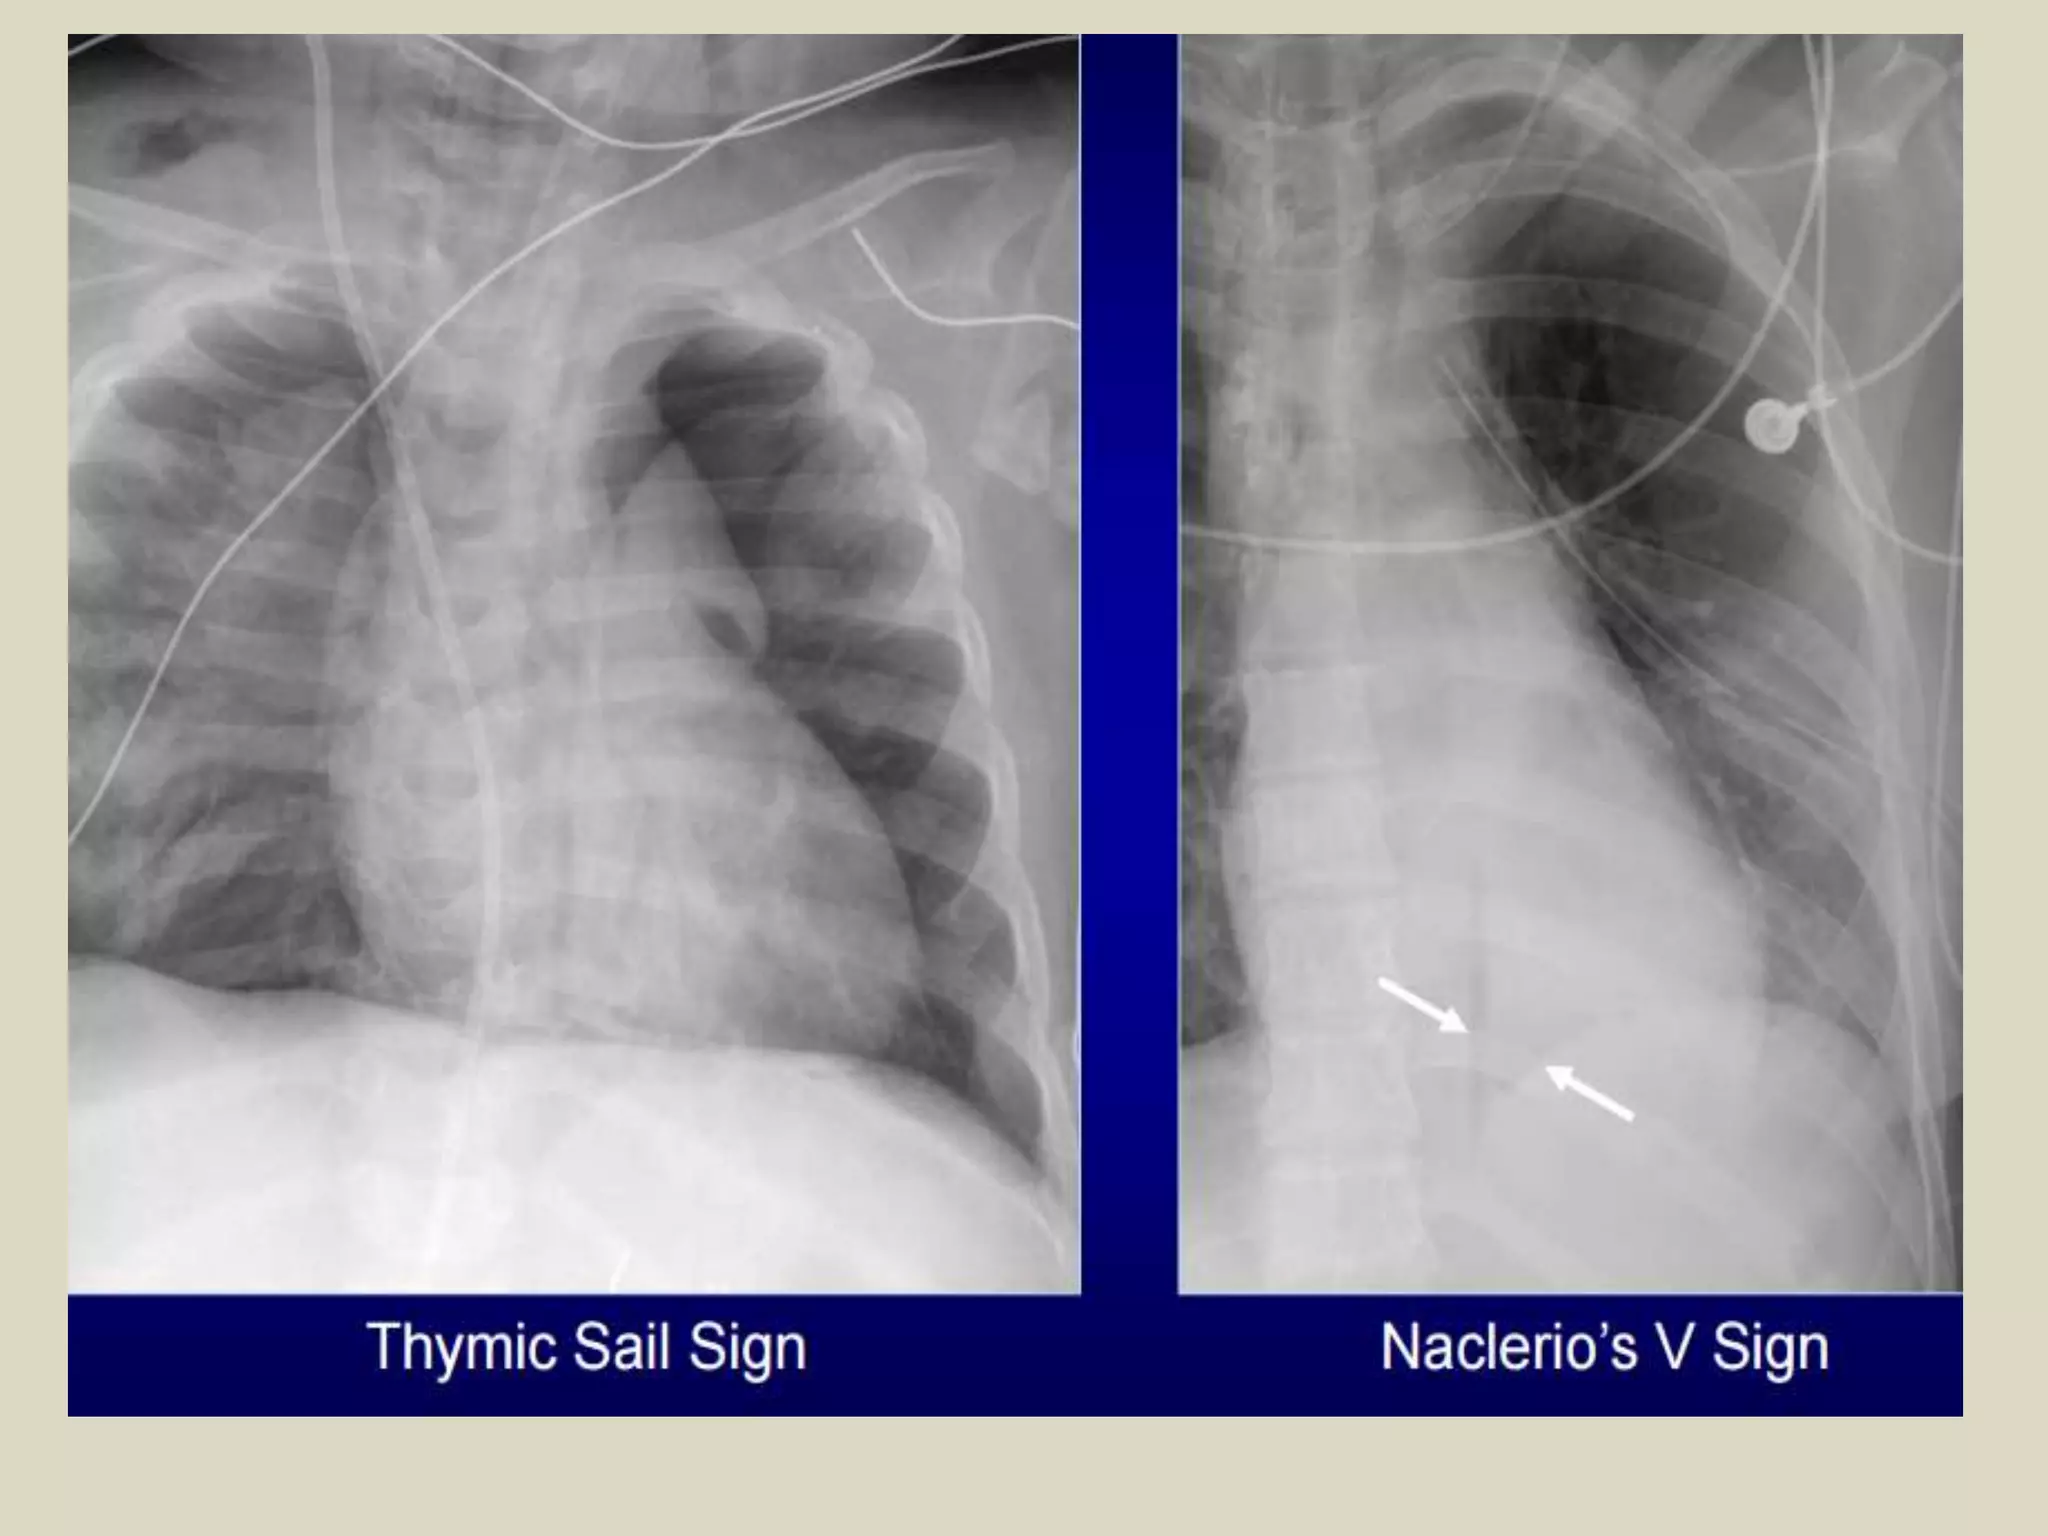

Ring Around Artery Sign

• Visualized on lateral chest radiographs

• Lucency along or surrounding RPA

• Characteristic of pneumomediastinum

• Usually is accompanied by other ancillary signs:

• continuous diaphragm sign

• Naclerio’s V sign

• thymic sail sign

Ring Around ArterySign • Visualized on lateral chest radiographs • Lucency along or surrounding RPA • Characteristic of pneumomediastinum • Usually is accompanied by other ancillary signs: • continuous diaphragm sign • Naclerio’s V sign • thymic sail sign